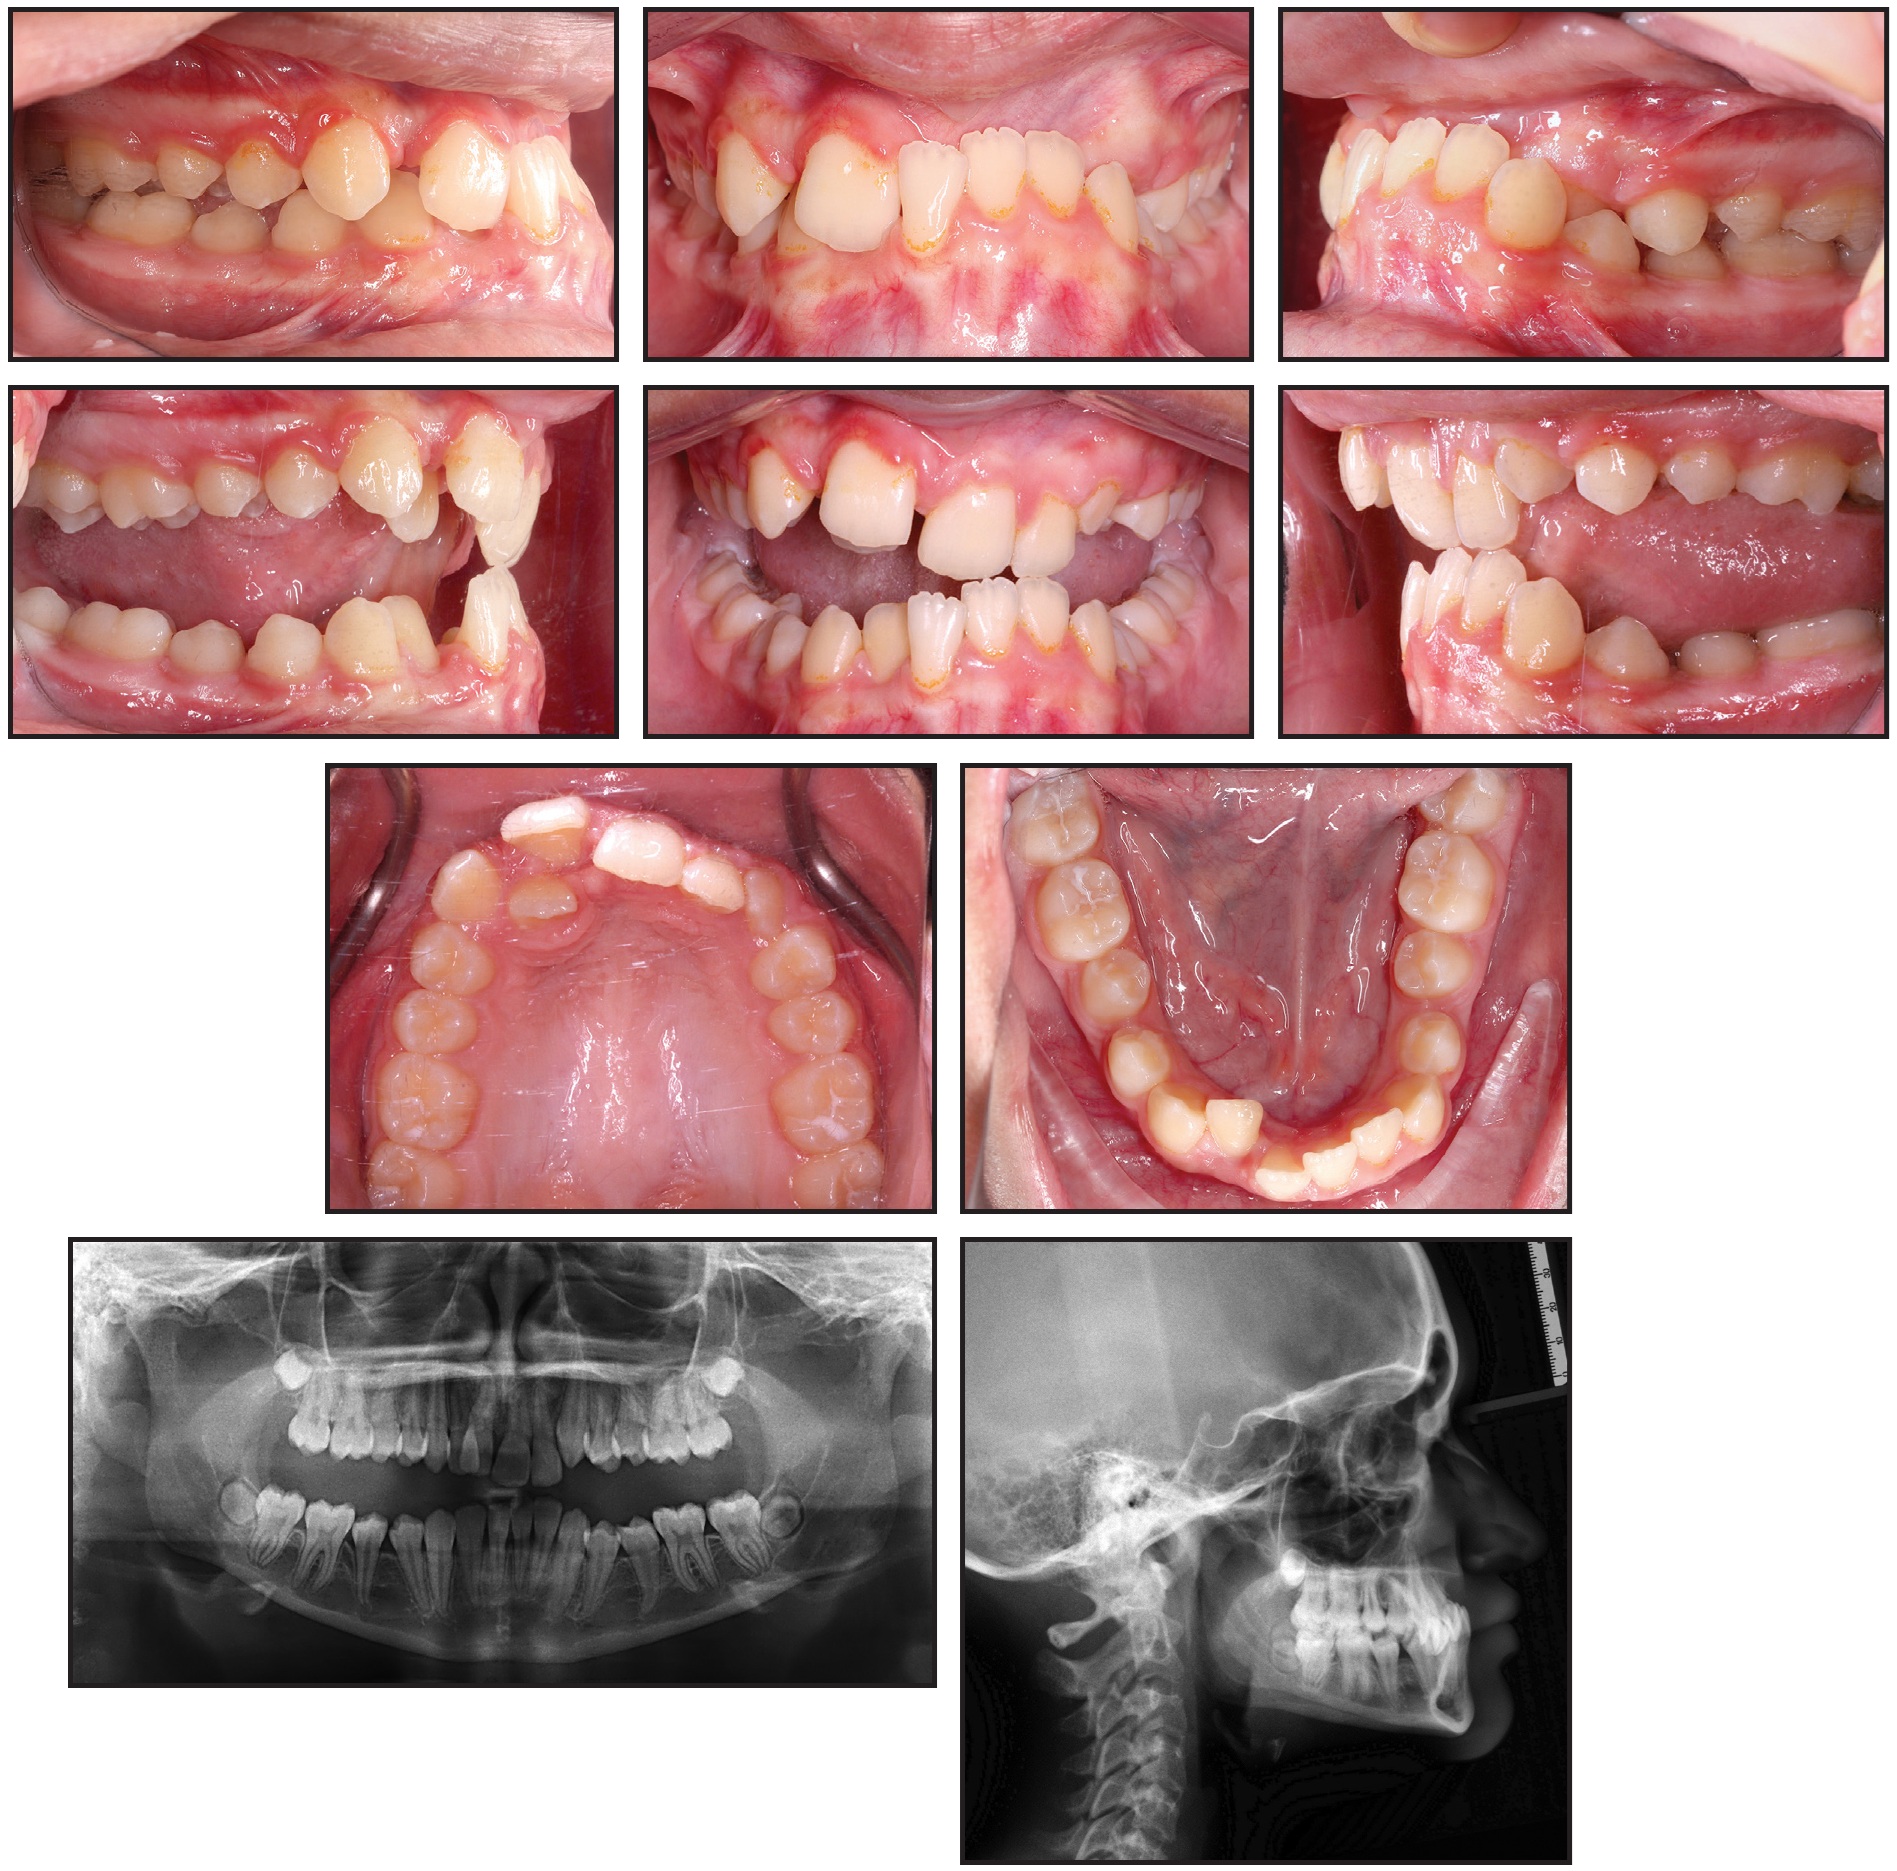

The patient presented with a skeletal Class III malocclusion, a hypodivergent growth pattern, and diminished lower anterior facial height. The smile arc was nonconsonant, with 70% incisal display in smiling. The maxillary midline was deviated 1.5mm to the right of the facial midline, and the mandibular midline was deviated 1.5mm to the left. An anterior crossbite was present at the upper right lateral incisor and from the upper left central incisor to the canine; due to premature contact at the incisors, a 2.5mm anterior functional shift between centric relation and maximum intercuspation was observed. The upper and lower right lateral incisors demonstrated grade 2 mobility. A 1.1mm Bolton discrepancy was attributable to a mandibular excess (Fig. 1A and 1B).

Fig. 1A Initial records (continued in next image).

Fig. 1 (cont.) Initial records.

Bilateral Class III molar relationships were present, along with a Class I canine relationship on the right; the canine relationship on the left could not be determined. The upper and lower incisors were retruded and retroclined. A severe deep bite (10.7mm) and negative overjet (–2.4mm) were noted. The curve of Wilson was exaggerated, as was the curve of Spee (5.5mm). Moderate crowding was present in the upper arch; the lower arch was tapered, with mild crowding.